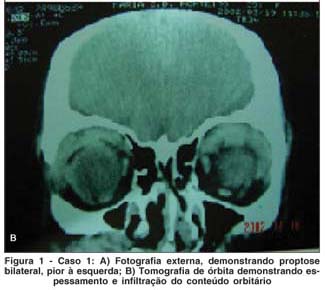

MCSM, 40 anos, sexo feminino, natural e procedente de São Paulo, aposentada. Queixa de " olhos saltados" há 5 anos. História pregressa: paciente acompanhada no departamento de Otorrinolaringologia por sinusite crônica, tendo sido submetida a 4 cirurgias em seios da face entre 1993 e 1997. Em 97, iniciou quadro de proptose bilateral, pior à esquerda, sendo feita hipótese diagnóstica de pseudotumor orbitário (Figura 1A). Foi tratada com prednisona em doses de até 80 mg/dia, com melhora parcial do quadro, mas com recidiva com a suspensão da medicação. Fez tratamento radioterápico em janeiro de 2000, apresentando melhora parcial do quadro. No período de acompanhamento, a paciente submeteu-se a uma série de biópsias para elucidação diagnóstica (incluindo biópsias de glândula lacrimal, pele palpebral e mucosa de seio maxilar) sem que se houvesse concluído a etiologia da doença. Há 18 meses, apresentava piora de edema em região maxilar direita. Há 15 meses, queixava-se de aumento da região submandibular. Exame oftalmológico: Proptose bilateral, maior à esquerda; Edema frio e xantelasma em pálpebra inferior de ambos os olhos; Motricidade ocular extrínseca e reflexos fotomotores sem alterações. Acuidade visual corrigida de 20/20 em ambos os olhos (Refração estática OD -3,00 DE; OE - 2,50 DE); Biomicroscopia: Ceratite puntata inferior leve em ambos os olhos. Pinguécula nasal em OE; Fundoscopia sem alterações em AO. Exames complementares: Tomografia de órbita com espessamento difuso da musculatura ocular extrínseca e aumento do volume de glândula lacrimal à esquerda (Figura 1A); Tomografia e ressonância de seios da face mostrando espessamento de mucosa em seio maxilar (Figura 1B); Ultra-sonografia de região cervical com sinais sugestivos de sialoadenite crônica das glândulas submandibulares e sublinguais. Linfonodos parotídeos aumentados. Pesquisa de anticorpos anti-citoplasma de neutrófilos (c-ANCA): positivo.